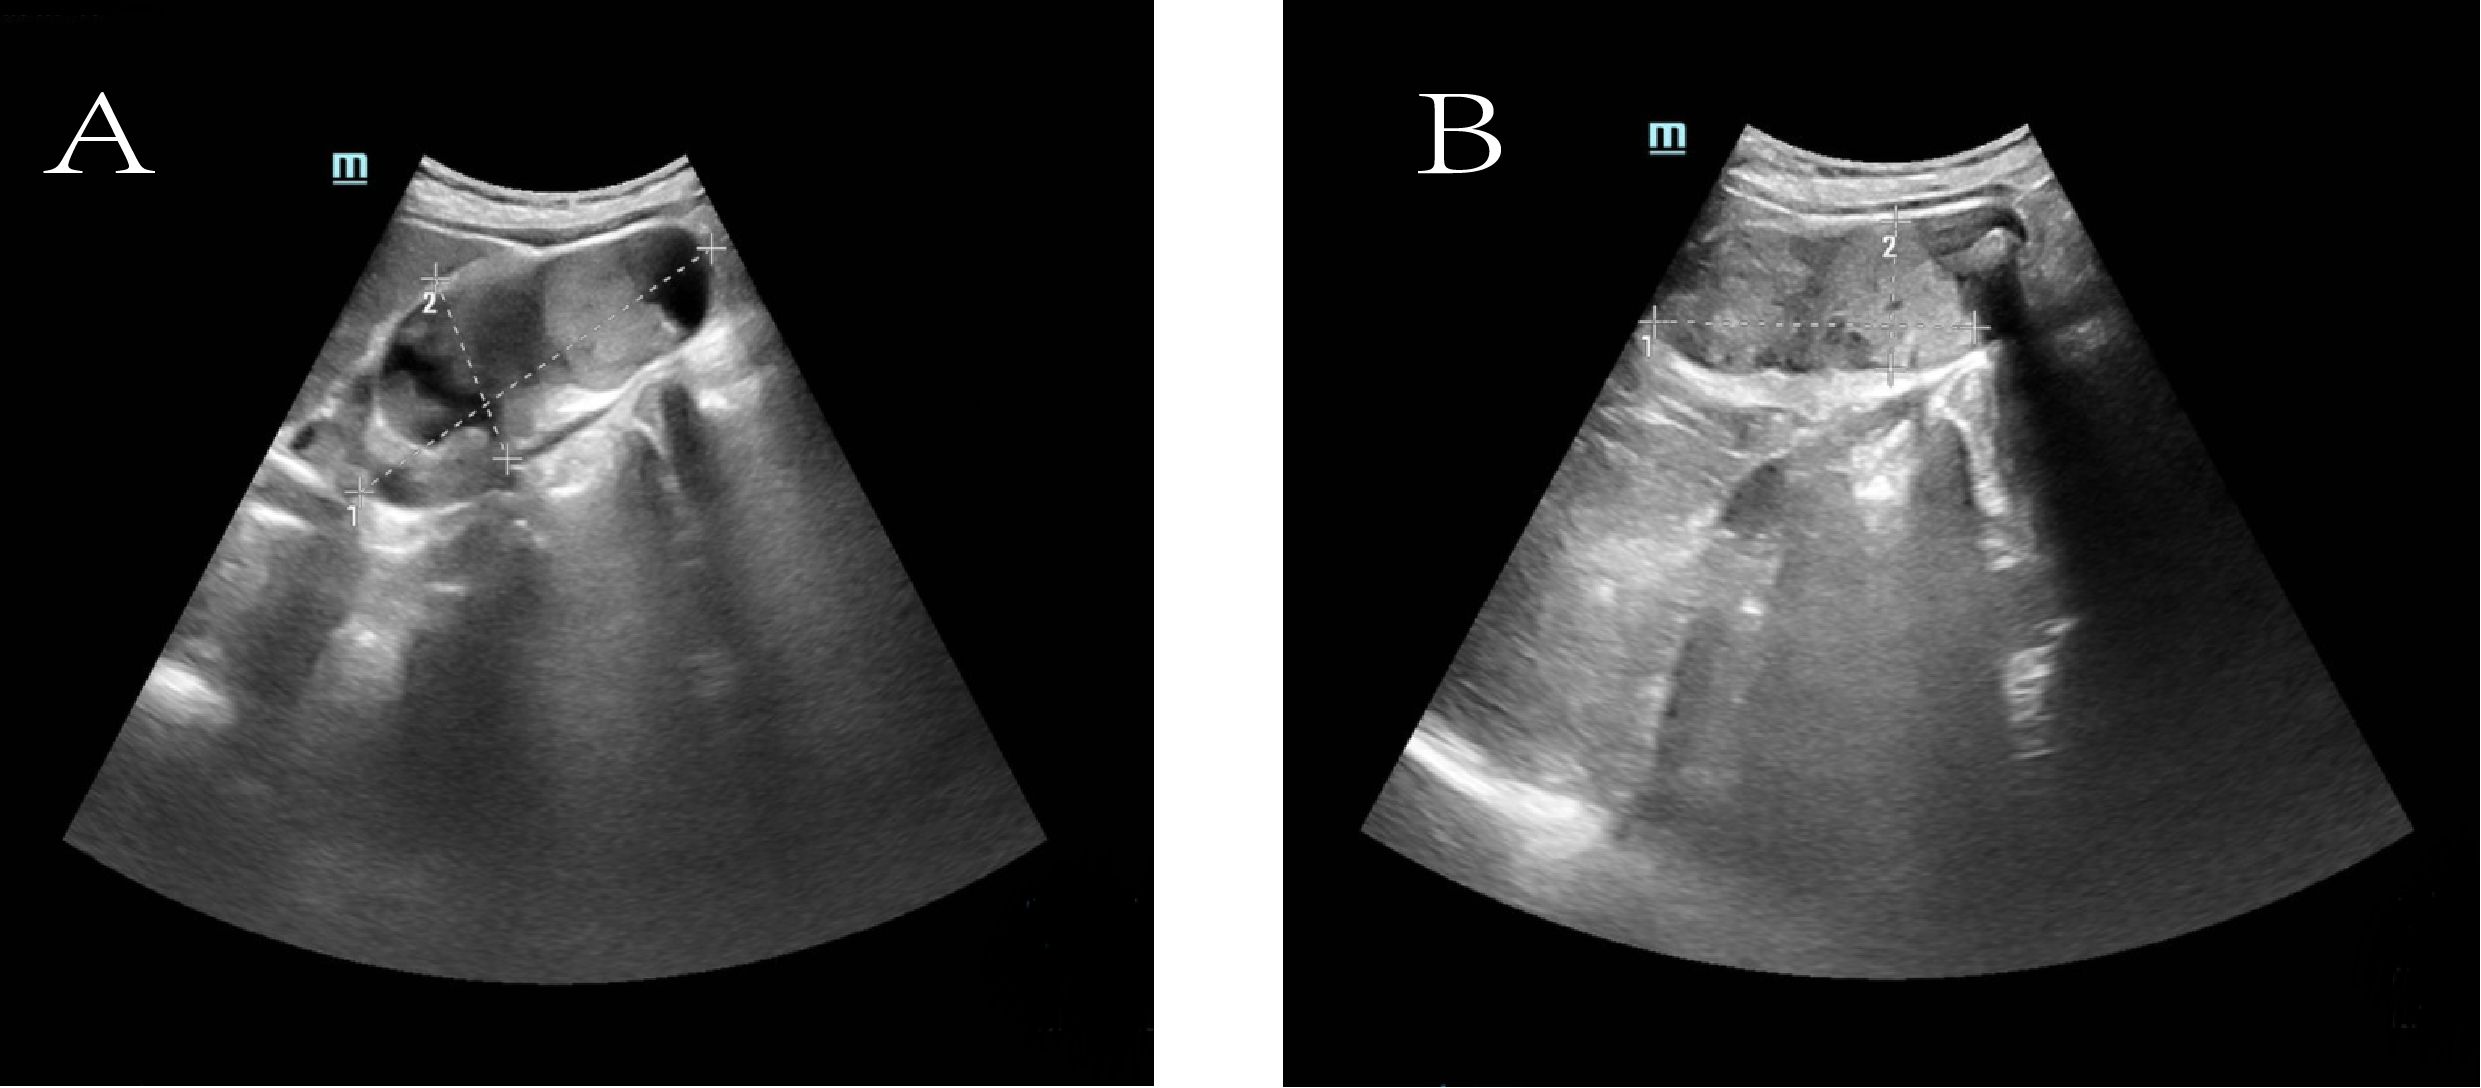

To further clarify the nature of the gallbladder mass, abdominal color Doppler ultrasound, upper abdominal contrast-enhanced CT, and PET-CT examinations were performed. Ultrasound revealed an enlarged gallbladder measuring approximately 9.7 × 4.2 cm with a moderately echogenic nodule filling its lumen, of indeterminate nature (See Figure 1). Contrast-enhanced CT showed increased gallbladder volume with localized uneven wall thickening and soft tissue density nodules protruding into the lumen, strongly suggesting neoplastic growth (Figure 2). Multiple nodular shadows were observed in the hepatic portal region, likely representing enlarged lymph nodes, with the largest measuring 1.9 × 1.7 cm. PET-CT confirmed increased retroperitoneal lymph nodes with elevated SUVmax values of approximately 18.0 and 25.9 on early and delayed imaging, respectively (Figure 3). These findings, showing both gallbladder soft tissue nodules and enlarged lymph nodes with abnormal metabolic activity, led to a preoperative diagnosis of gallbladder carcinoma with hepatic portal lymph node metastasis.

Contrast-enhanced abdominal CT reveals key findings: an enlarged gallbladder with irregular wall thickening and an enhancing intraluminal nodule; multiple enhancing hilar nodules, the largest measuring 1.9 x 1.7 cm; and mild intrahepatic and proximal common bile duct dilatation.

Figure 2. Contrast-enhanced computed tomography (CT). (A) Arterial phase image shows the mass (white arrow). (B) Venous phase image of the same mass (white arrow).